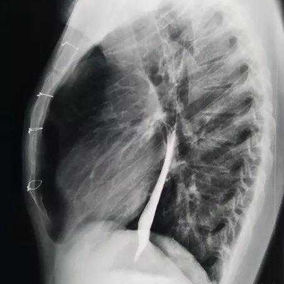

Preoperative Examination

The chest wall exhibits a large area of prominent and bilaterally symmetrical protrusion, predominantly in the upper half. There are also mild depressions on both sides of the lower half of the chest wall.

First, two 3 cm incisions were made on each side of the chest wall, followed by a 2 cm incision along the old surgical scar in the middle of the chest wall. Two bars were then placed on the protruding bone structures of the chest wall to perform the Wenlin procedure. Since the anterior chest wall is a rigid whole, correcting and pressing down the protrusion in the upper chest often causes a secondary depression below it. To address this, a third bar was inserted into the chest cavity to perform the Wung procedure, thereby elevating the depressed areas. Ultimately, the patient’s chest wall deformity was corrected, and the surgery achieved a satisfactory outcome.